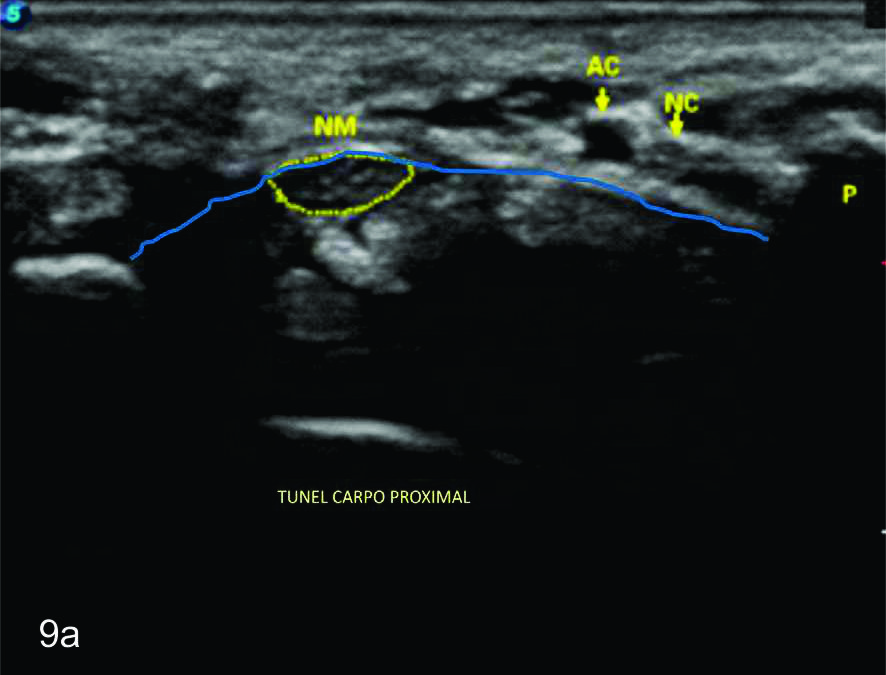

Figura 9

Nervio mediano

Cortes axiales en el nivel del túnel del carpo, se identifica al nervio mediano dentro de la elipse amarilla. A- Túnel proximal, al nivel del hueso pisciforme (P), B- Túnel distal, entre el túberculo del trapecio (TT) y el gancho del hueso ganchoso (GG). AC- Arteria cubital, NC- Nervio cubital, Línea azul- ligamento anular del carpo.